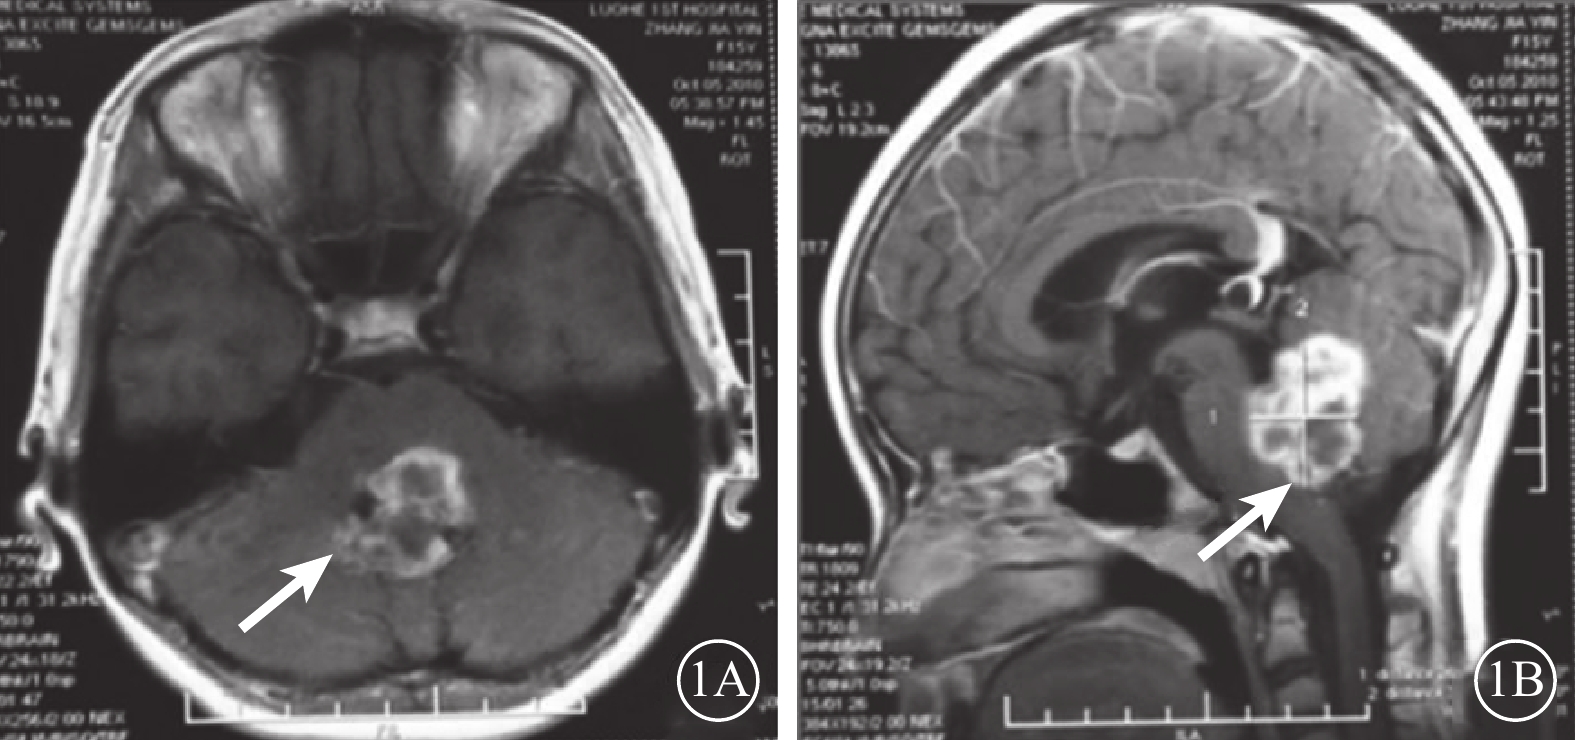

患者女,18歲。2010年9月因頭枕部外傷致意識喪失入院。醒后發現左眼內斜、眼球運動障礙、視力下降伴口角右偏。眼眶CT檢查未見異常;頭顱MRI檢查顯示小腦蚓部出血致雙側小腦半球、第四腦室及背側腦橋受壓變形(圖1)。傷后10 d行顱內血腫清除手術。手術后上述癥狀無改善且逐漸出現左眼瞼閉合不全、視力逐漸下降。為求進一步診治于2015年12月到我科就診。否認既往眼病及全身病史。眼部檢查:右眼視力1.0;左眼視力0.1,不能矯正。雙眼瞳孔等大,對光反射靈敏;左眼相對性瞳孔傳入性障礙(+)。雙眼視盤邊界清楚,顏色淡,以左眼為著;黃斑中心凹反光清晰。雙眼眼壓正常。視野檢查,右眼生理盲點擴大,鼻下象限視野部分缺損,視敏度下降;左眼顳側及鼻上象限視野不規則缺損。光相干斷層掃描檢查,雙眼視盤周圍視網膜神經纖維層變薄。眼位檢查,右眼注視時左眼內斜約30°;左眼注視不良。眼球運動檢查,右眼外展正常伴輕度水平眼球震顫,內收受限,鼻側角膜緣僅到達上、下淚小點連線;左眼外展受限,顳側角膜緣剛過中線,內收正常(圖2),單眼和雙眼運動相同;輻輳反射正常。神經系統檢查,左側額紋消失,瞼裂閉合不全,鼻唇溝變淺,舌前2/3味覺減退;口角向右偏斜,鼓腮時左側漏氣。診斷:(1)麻痹性內斜視;(2)非典型性八個半綜合征;(3)外傷性視交叉病變;(4)雙眼視神經萎縮。行左眼上、下直肌1/2轉位聯合內直肌后退手術。手術后眼位正,隨訪半年眼位穩定。

頭顱MRI像。1A. 平掃軸位T1像;1B. 增強掃描矢狀位T1像。小腦蚓部出血導致第四腦室及背側腦橋受壓變形(白箭)

頭顱MRI像。1A. 平掃軸位T1像;1B. 增強掃描矢狀位T1像。小腦蚓部出血導致第四腦室及背側腦橋受壓變形(白箭)

本例患者頭枕部外傷導致顱內小腦蚓部出血,第四腦室和背側腦橋受壓,損傷左側腦橋側視中樞和面神經膝,繼而患側眼球不能外展但內收正常,健側眼球內收受限但外展正常,同時合并患側周圍性面癱。由于缺少患側內側縱束損傷,故為非典型性八個半綜合征。患者損傷部位定位在左側腦橋尾部被蓋區,但病變僅累及患側側視中樞和面神經膝,未波及患側內側縱束。但若患側內側縱束未遭受任何侵害,則患者健眼外展時不應出現水平眼震。而本例患者健眼外展時伴有眼震,其原因可能是患側內側縱束輕微損害導致對患眼內直肌興奮性神經纖維和健眼內直肌抑制性神經纖維的支配減弱,使得健眼內直肌的興奮性增高,但未表現出患眼內收運動障礙。另外,患者雙眼視野損傷及左側為著的雙側視神經萎縮應為視交叉左后下方受損所致。

患者女,18歲。2010年9月因頭枕部外傷致意識喪失入院。醒后發現左眼內斜、眼球運動障礙、視力下降伴口角右偏。眼眶CT檢查未見異常;頭顱MRI檢查顯示小腦蚓部出血致雙側小腦半球、第四腦室及背側腦橋受壓變形(圖1)。傷后10 d行顱內血腫清除手術。手術后上述癥狀無改善且逐漸出現左眼瞼閉合不全、視力逐漸下降。為求進一步診治于2015年12月到我科就診。否認既往眼病及全身病史。眼部檢查:右眼視力1.0;左眼視力0.1,不能矯正。雙眼瞳孔等大,對光反射靈敏;左眼相對性瞳孔傳入性障礙(+)。雙眼視盤邊界清楚,顏色淡,以左眼為著;黃斑中心凹反光清晰。雙眼眼壓正常。視野檢查,右眼生理盲點擴大,鼻下象限視野部分缺損,視敏度下降;左眼顳側及鼻上象限視野不規則缺損。光相干斷層掃描檢查,雙眼視盤周圍視網膜神經纖維層變薄。眼位檢查,右眼注視時左眼內斜約30°;左眼注視不良。眼球運動檢查,右眼外展正常伴輕度水平眼球震顫,內收受限,鼻側角膜緣僅到達上、下淚小點連線;左眼外展受限,顳側角膜緣剛過中線,內收正常(圖2),單眼和雙眼運動相同;輻輳反射正常。神經系統檢查,左側額紋消失,瞼裂閉合不全,鼻唇溝變淺,舌前2/3味覺減退;口角向右偏斜,鼓腮時左側漏氣。診斷:(1)麻痹性內斜視;(2)非典型性八個半綜合征;(3)外傷性視交叉病變;(4)雙眼視神經萎縮。行左眼上、下直肌1/2轉位聯合內直肌后退手術。手術后眼位正,隨訪半年眼位穩定。

頭顱MRI像。1A. 平掃軸位T1像;1B. 增強掃描矢狀位T1像。小腦蚓部出血導致第四腦室及背側腦橋受壓變形(白箭)

頭顱MRI像。1A. 平掃軸位T1像;1B. 增強掃描矢狀位T1像。小腦蚓部出血導致第四腦室及背側腦橋受壓變形(白箭)

本例患者頭枕部外傷導致顱內小腦蚓部出血,第四腦室和背側腦橋受壓,損傷左側腦橋側視中樞和面神經膝,繼而患側眼球不能外展但內收正常,健側眼球內收受限但外展正常,同時合并患側周圍性面癱。由于缺少患側內側縱束損傷,故為非典型性八個半綜合征。患者損傷部位定位在左側腦橋尾部被蓋區,但病變僅累及患側側視中樞和面神經膝,未波及患側內側縱束。但若患側內側縱束未遭受任何侵害,則患者健眼外展時不應出現水平眼震。而本例患者健眼外展時伴有眼震,其原因可能是患側內側縱束輕微損害導致對患眼內直肌興奮性神經纖維和健眼內直肌抑制性神經纖維的支配減弱,使得健眼內直肌的興奮性增高,但未表現出患眼內收運動障礙。另外,患者雙眼視野損傷及左側為著的雙側視神經萎縮應為視交叉左后下方受損所致。